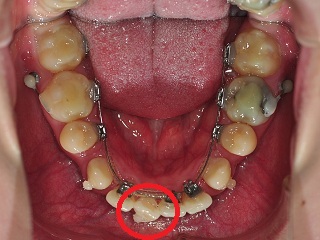

고르지 못하고 튀어나와있는 하악 앞니에 보조장치를 부착하였습니다.

이것으로 이동을 시키겠죠?

참 신기한 것이.. 앞니에 보조장치 부착하고 고무줄로 감아 당겨주셨는데,

와우저동그랗고작은보조장치는뭔가요??대박 신기해요!

저도 이름이 궁금해서 치위생사쌤께 물어봤는데, 그게 어려운 전문적인 용어였어요;; ㅋㅋㅋㅋ

저 보조장치에 연결하여 삐뚤어진 치아를 돌리는 거구용~

클립버튼인가.. 그렇게 부른다는 거 같아요~